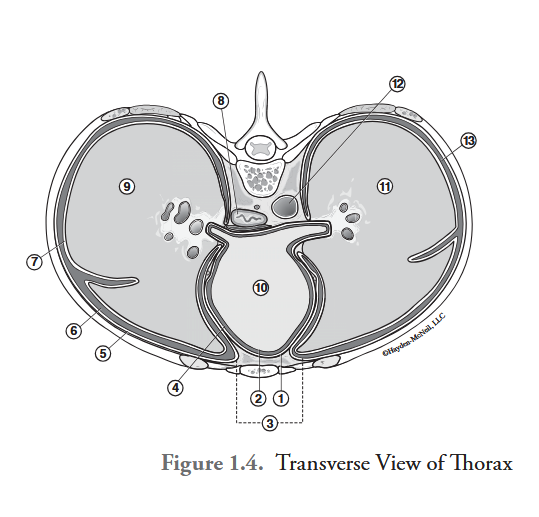

What is labeled #1?

parietal pericardium

What is labeled #2?

visceral pericardium (epicardium)

What is labeled #3?

mediastinum

What is labeled #4?

pericardial cavity

What is labeled #5?

parietal pleura

What is labeled #6?

right pleural cavity

What is labeled #7?

visceral pleura

What is labeled #8?

esophagus

What is labeled #9?

right lung

What is labeled #10?

heart

What is labeled #11?

left lung

What is labeled #12?

descending aorta

What is labeled #13?

left pleural cavity